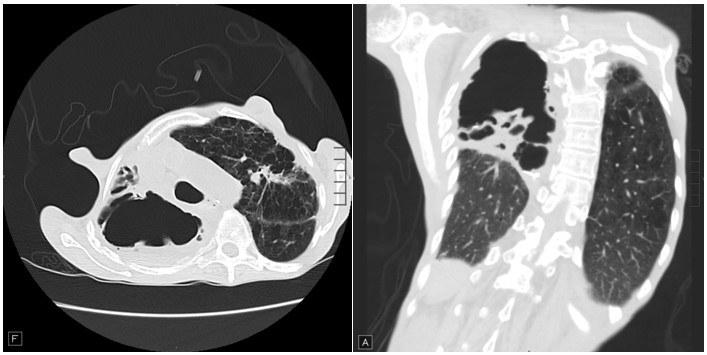

On exam, he was afebrile but tachycardic with heart rate of 105 beats/minute and tachypneic with respiratory rate of 22 breaths/minute. He was not in any significant distress. His lung exam was significant for decreased breath sounds in all lung fields with prominent hyperresonance in right upper lung fields. He had finger clubbing and evidence of fat and muscle wasting. Chest X-ray shows air fluid levels in right upper lung spaces. Sputum cultures were obtained. Images from his high-resolution CT scan of Chest are shown below: